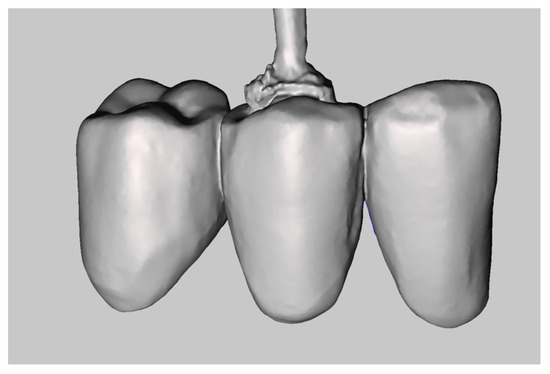

- Step C: Creation of the Master Model

Using MeshMixer, it is possible to detect and delete superimposed areas not intended to be part of the master model (Figure 11). From the abutment scan, we retain the coronal and medial third of the prepared teeth, whereas from the scan of the provisional restoration, we use the sulcus and finish line data (Figure 12 and Figure 13). Using the MeshMixer “Join” tool, we fuse the data in the two original STL files into a single, merged file (Figure 14), representing the subgingival zone. The final step is to match this file to the direct scan of the abutment. Then we import the file into Exocad and substitute the abutments of the original scan with the new ones that include more precise information on the subgingival zone. This last step is performed using the “Multi-die” tool (Figure 15). This method generates a master model in Exocad (Figure 16). When modelling the definitive restoration, the dental technician should consider that the master scan of the abutments, derived from the provisional restoration, does not provide information on the luting agent’s thickness. The operator should add this space using CAD software.

Figure 13.

Subgingival zone derived from the scan of the provisional restoration.

Figure 14.

Deriving a unified file from two separate parts.